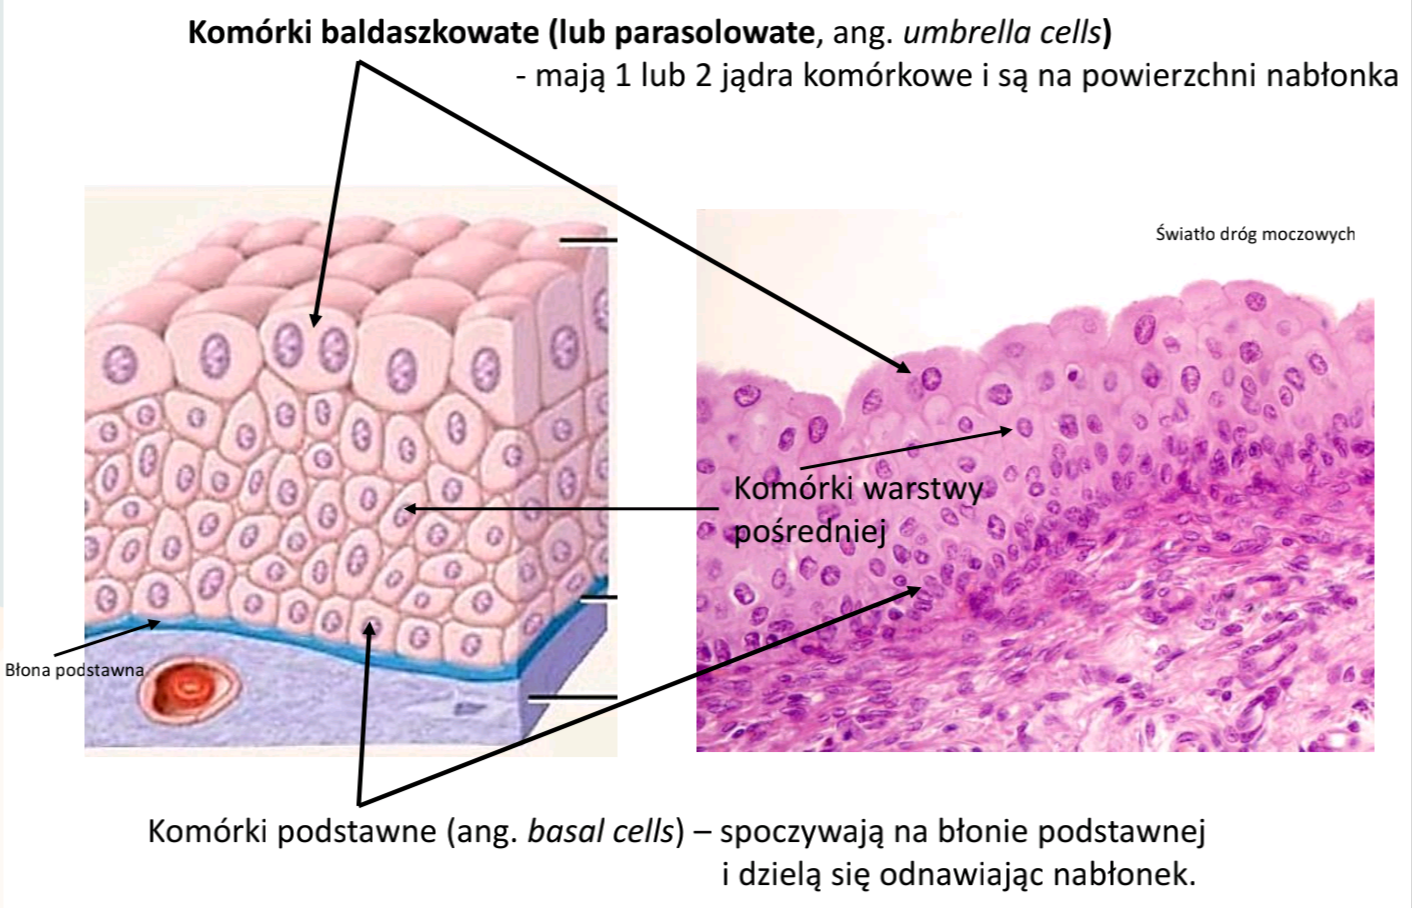

Nabłonek przejściowy, inaczej nazywany urotelium

Gdzie?- Występuje w większej części dróg moczowych: kielichy nerkowe, moczowody, pęcherz moczowy, początkowy odcinek cewki moczowej.

Czym jest urotelium?

Na powierzchni tego nabłonka (wyściełanie światła dróg moczowych) znajdują się komórki baldaszkowate, zwane także parasolowatymi (ang. umbrella cells). Jak szerokie baldachimy, albo parasole, pokrywają mniejsze głębiej położone pozostałe komórki nabłonka. Komórki baldaszkowe tworzą barierę dla toksyn znajdujących się w moczu (pokryte są glikokaliksem i specyficznymi białkami barierowymi jak uroplakiny)oraz mają zdolność silnego rozciągania się (ważne dla wypełniania się pęcherza moczem).